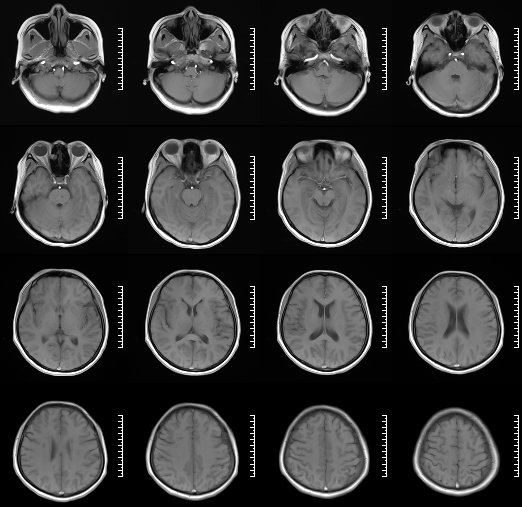

术前影像

HRMRI

左侧脑室旁亚急性期-慢性期脑梗死